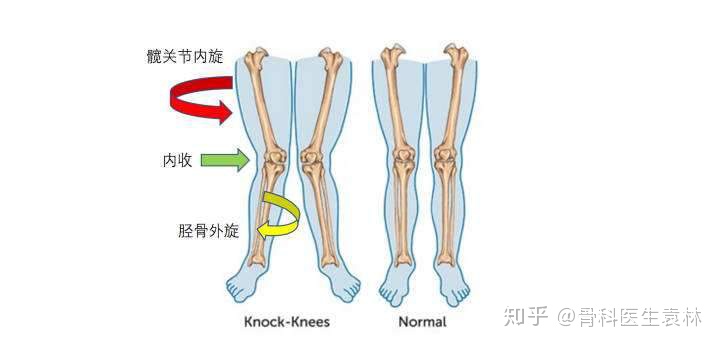

虽然膝关节这四大韧带都有损伤的风险,但是有一种损伤却是我们跑步中特别需要提防、也是可以有效通过人为干预的:膝关节内扣(大腿向内扣,小腿向外翻)引起的韧带损伤。膝关节内扣的具体姿态如下图:

膝关节内扣

因为膝关节在这种内扣的姿态下,是极度不稳定的,这时候身体重心位于支撑腿的内侧,胫骨极易在重力的作用下过度外翻,对内侧副韧带、前交叉韧带都造成很大的负担容易造成它们的断裂。那么,该通过什么手段来减少膝关节内扣的习惯呢?

越来越多的研究表明,髋外展肌群(髋部外侧)肌力不足,对于膝关节甚至踝关节的影响比股四头肌薄弱的影响严重的多。髋部外侧的臀中肌,功能是稳定骨盆、使髋关节外展,并阻止大腿过度内收内旋,从而稳定髋关节。当臀中肌薄弱时,大腿容易过度内收内旋,导致膝关节内扣

所以,加强髋外侧力量训练,是减轻膝关节内扣现象、加强膝关节稳定性的重要手段,从而可以保护膝关节韧带。